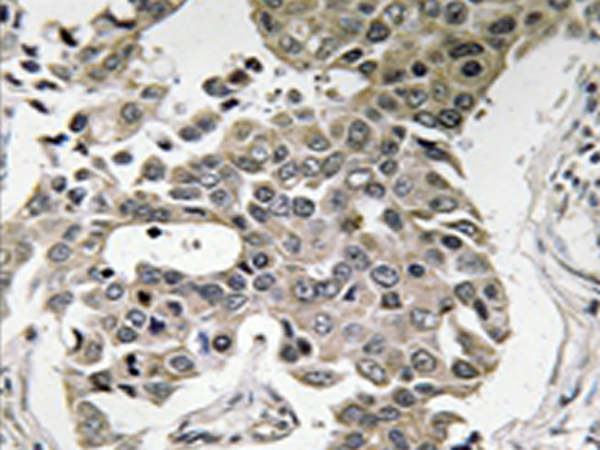

IHC positive control: |

Human breast carcinoma tissue |

IHC Recommend dilution: |

50-100 |